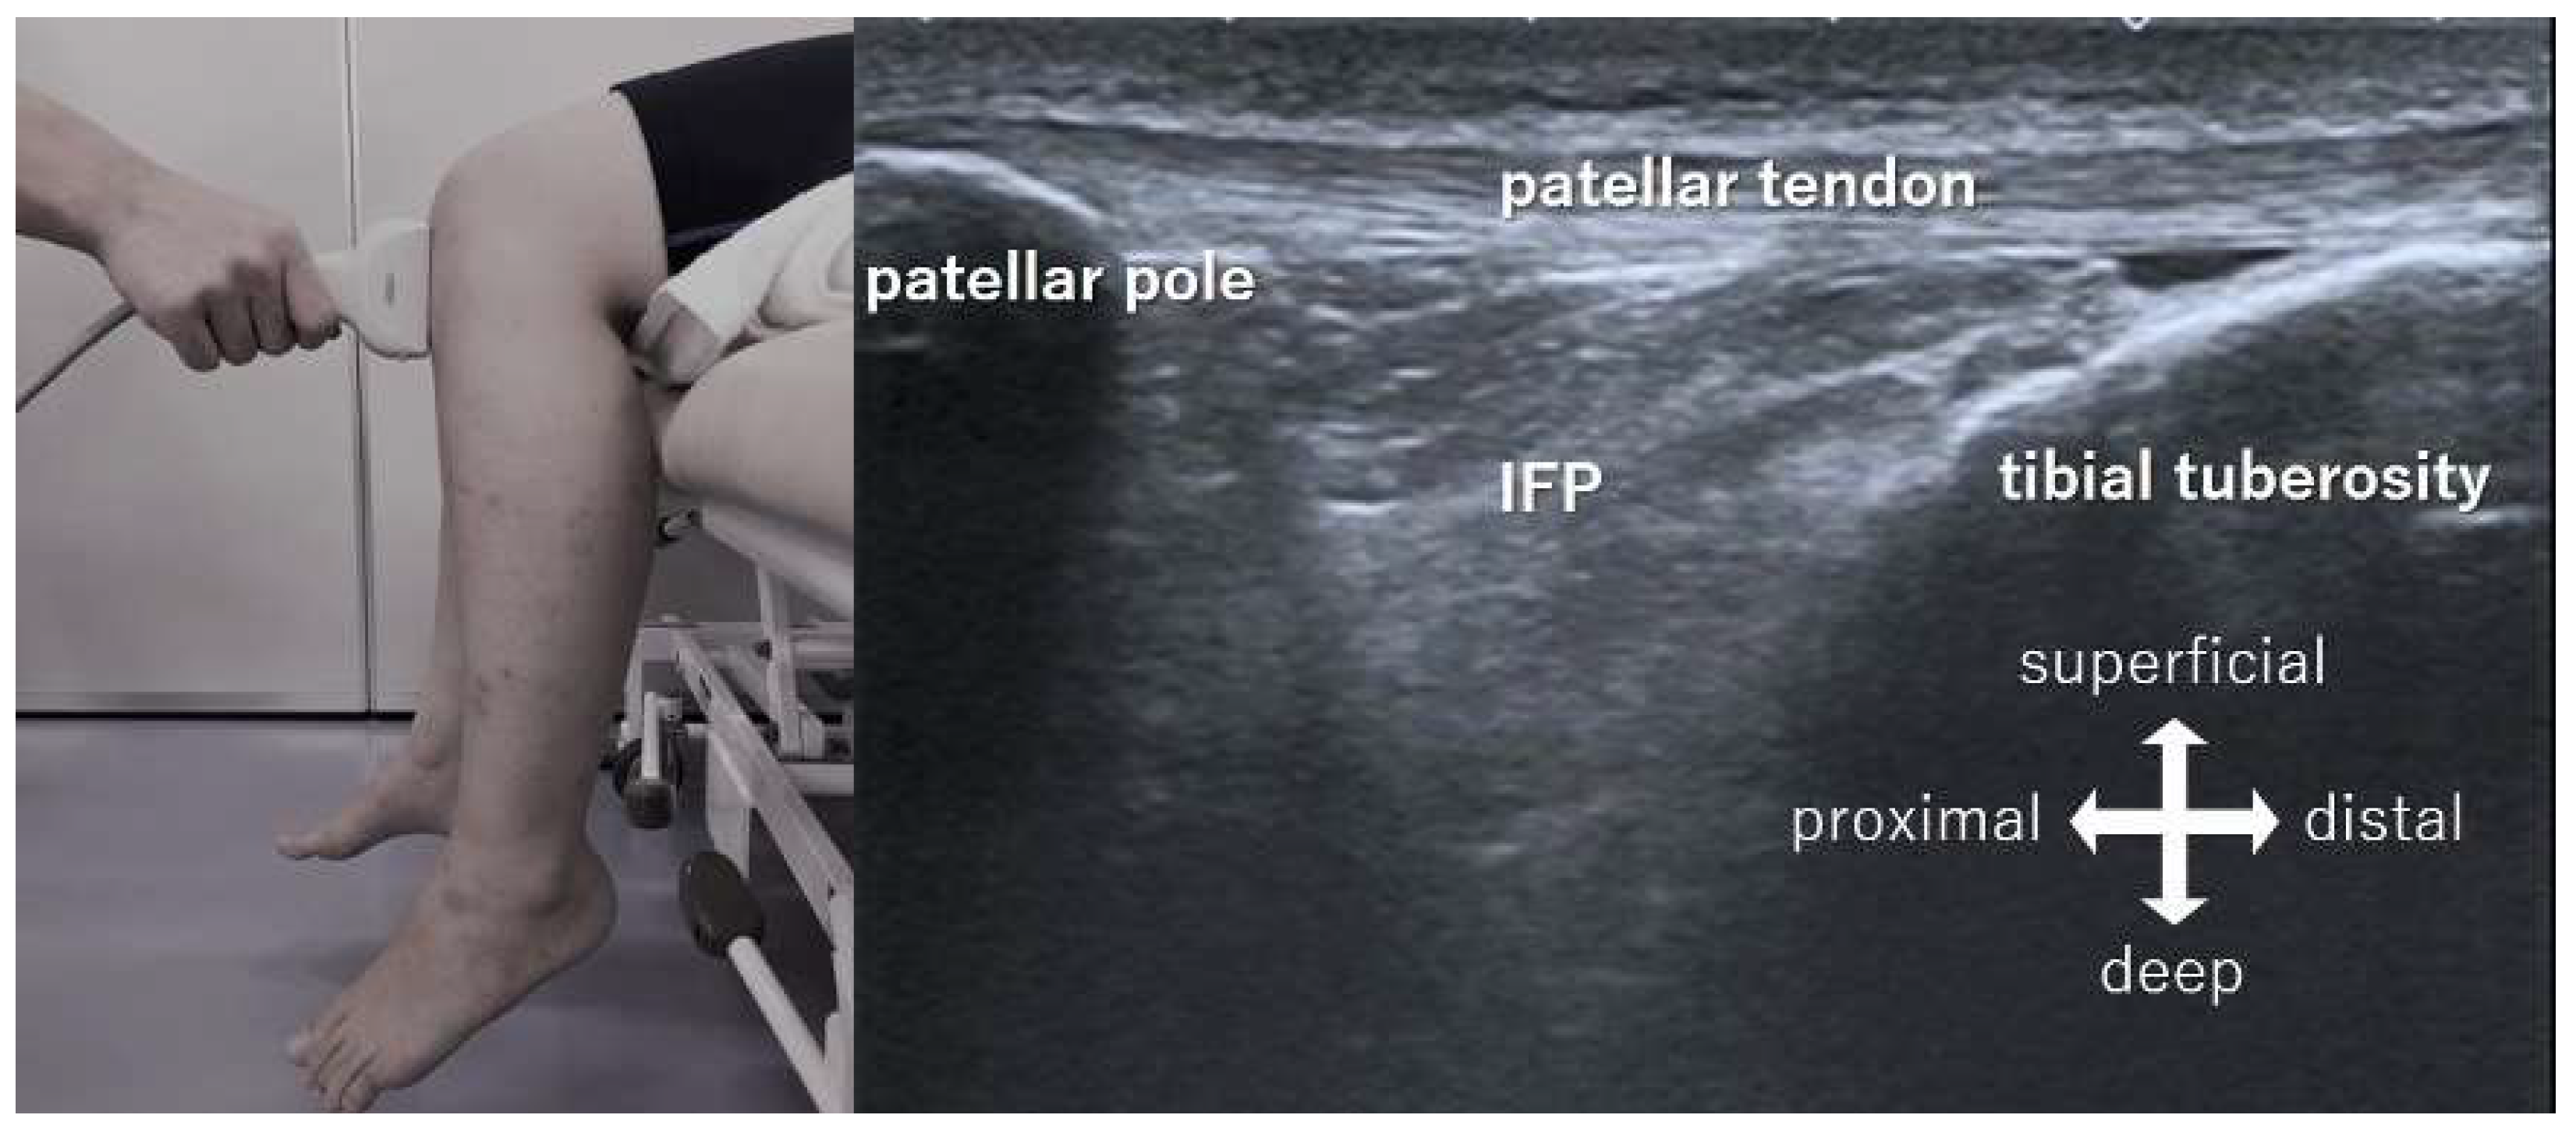

2. Methods

2.1. Procedures